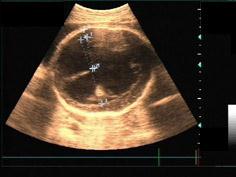

36周胎儿头部超声检查如图,根据声像图初步诊断应该为 ( )A、孔洞脑B、小脑蚓部缺损C、脑积水D、先天性蛛网膜囊肿E、无脑畸形

问题 36周胎儿头部超声检查如图,根据声像图初步诊断应该为 ( )

选项 A、孔洞脑 B、小脑蚓部缺损 C、脑积水 D、先天性蛛网膜囊肿 E、无脑畸形

答案 C